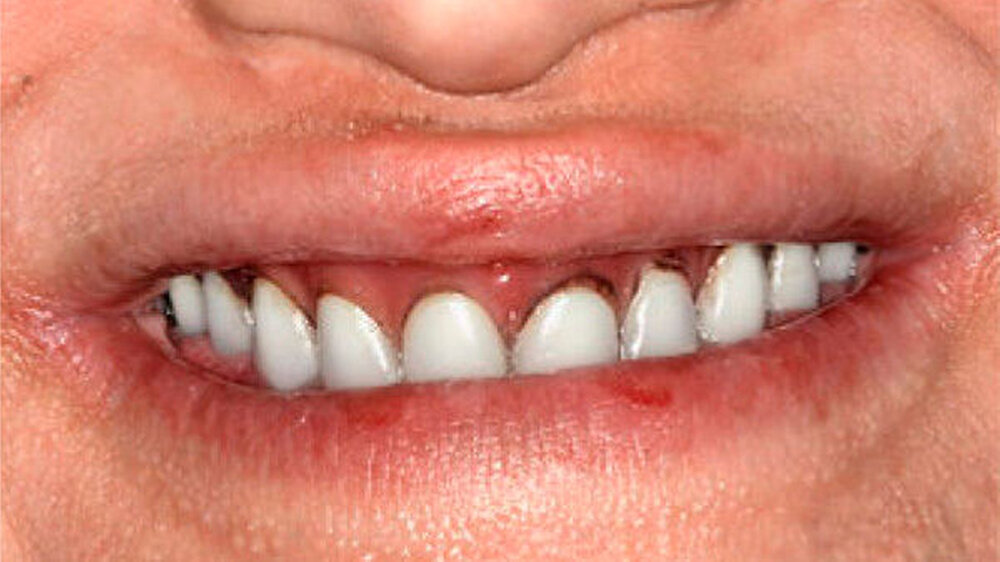

Bei dieser bei Behandlungsbeginn 16-jährigen Patientin waren seit Geburt nur die beiden ersten Molaren im Oberkiefer ausgebildet. Die Folge waren schmale und niedrige Alveolarkämme mit einem flachen Gaumengewölbe (Abb. 16 und 17). Die röntgenologische Abbildung bestätigte das geringe vertikale Knochenangebot. Eine Formanomalie der Zahnwurzeln ließ auf taurodonte Molaren schließen. Beide Molaren wiesen ausgedehnte kariöse Läsionen auf (Abb. 18).

Die Patientin war mit einer knapp neunjährigen Teilprothese im Ober- und einer zweijährigen Totalprothese im Unterkiefer versorgt. Beim Lachen wurden die nicht mehr altersentsprechenden Prothesenzähne mit den deutlichen Randverfärbungen ersichtlich (Abb. 19). Das sagittale Wachstum des zahnlosen Unterkiefers führte in den letzten zwei Jahren aufgrund der verstärkten Kontakte im Frontzahnbereich zu einer beidseitigen Nonokklusion im Seitenzahnbereich (Abb. 20). Eine rasche Verbesserung der Ästhetik als auch der Funktion war unbedingt angezeigt, um das Selbstbewusstsein dieses puberalen Mädchens zu stärken.